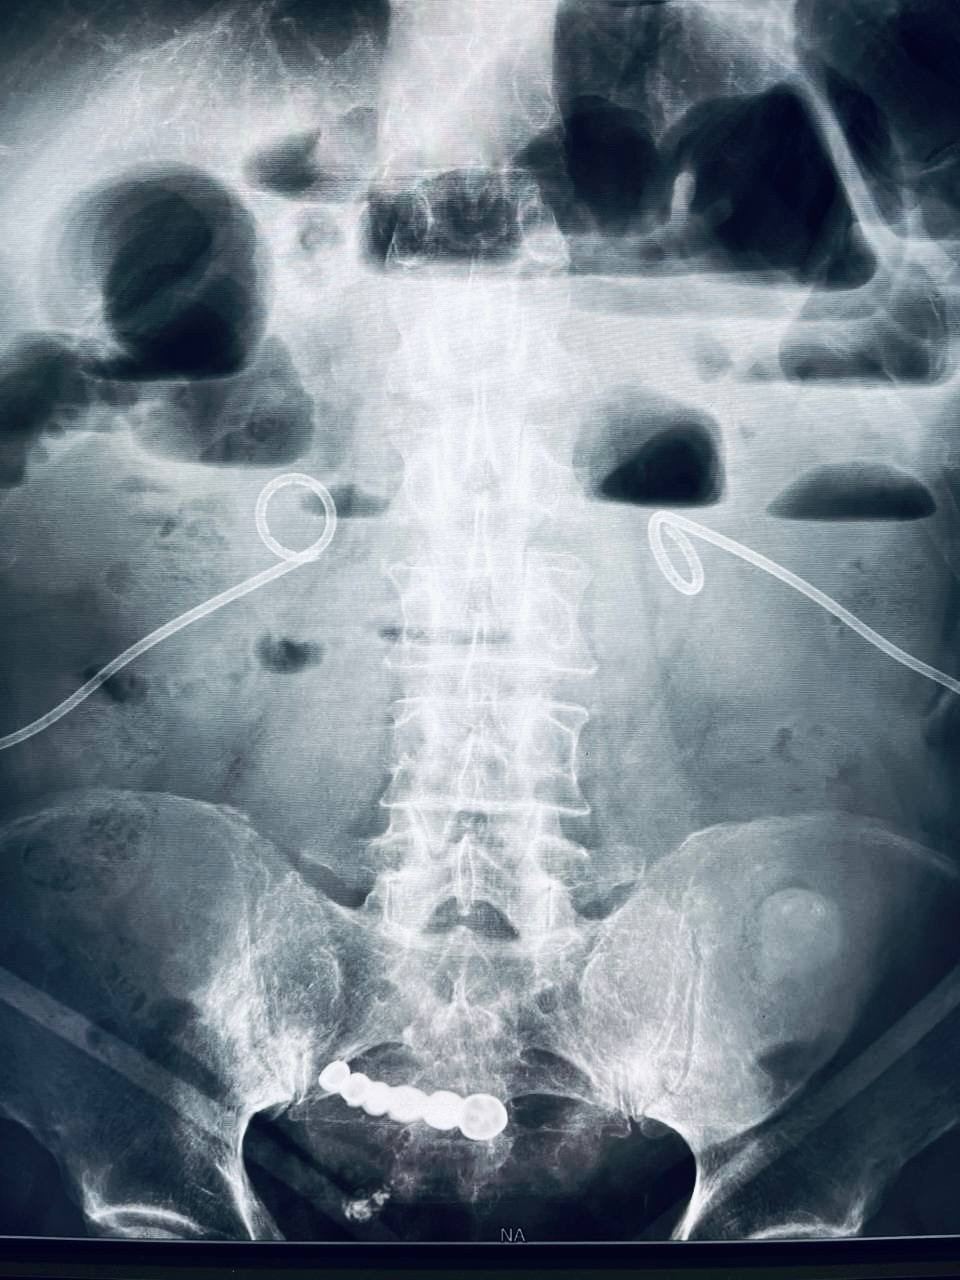

Житель Кузбасса проглотил вставную челюсть и шесть лет прожил с ней в животе.

Изначально мужчина не испытывал боли и не обращался к врачам, однако спустя шесть лет появились болевые ощущения. В результате протез был успешно удален хирургами.